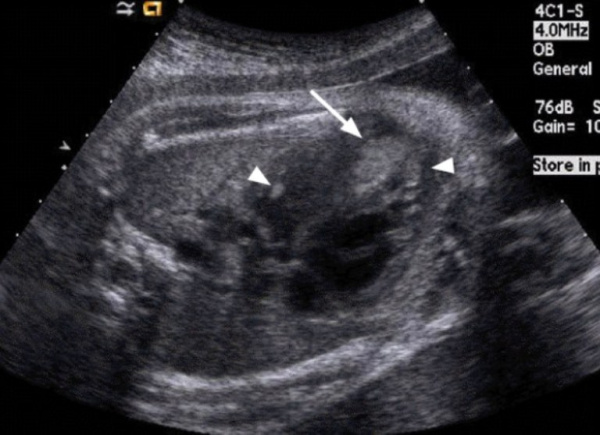

(Слева) Четырехкамерный срез сердца. Определяется очень крупное образование, поражающее всю свободную стенку ПЖ. Опухоль не вызывает обструкцию входного отдела, о чем свидетельствует отсутствие изменений ТК. В области верхушки ЛЖ визуализируются другие образования.

(Справа) Срез по длинной оси. Определяются крупное образование в области верхушки ЛЖ и небольшое образование в толще перегородки. Полость ЛЖ не уменьшена, обструкция входного или выходного отделов отсутствует. В данном случае рабдомиомы регрессировали после рождения ребенка.